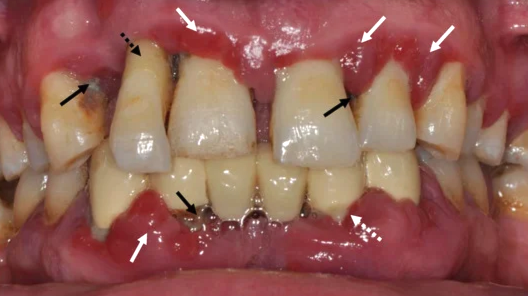

육안으로 보았을 때는

표면에 나타난 충치나 잇몸의 부종, 염증 등은

파악할 수 있으나,

치아 뿌리, 치경부, 치조골 소실 정도 등은

쉽게 식별되지 않습니다.

b. 치주 질환

스케일링만으로는 제거가

어려운 잇몸 아래 치석이 다량으로 쌓였을 때는

이를 통해 그 위치와 양을 정확하게

확인이 가능하며, 상담자료로 할 수 있습니다.

또한, 치조골 손실이나

잇몸(치은) 주위의 염증 상태를 관찰하여,

증세가 나타나기 전에

치주염 등 치주 질환의 진행 가능성을

예측할 수 있죠.